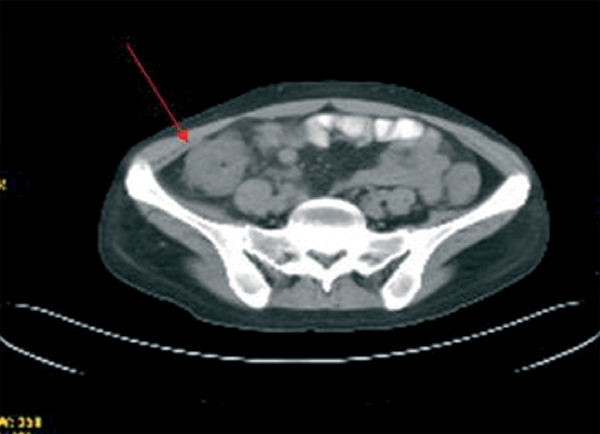

Durante el ingreso, la paciente desarrolló fiebre, dolor abdominal, vómitos y deposiciones diarreicas. Se realizaron coprocultivos, estudio de parásitos, determinación de toxina para Clostridium difficile y antigenemia para citomegalovirus (CMV) en dos ocasiones, que resultaron negativas. Se realizó TC abdominal (figura 1) en la que se observó engrosamiento de la pared del colon con oclusión de la luz desde el ciego hasta la unión recto-sigmoidea compatible con pancolitis difusa. Se solicitó fibrocolonoscopia (figura 2) en la que se objetivó una mucosa edematosa con múltiples lesiones nodulares blandas compatibles con neumatosis coli. En la biopsia de colon se detectaron inclusiones víricas que se confirmaron para CMV por inmunohistoquímica (figura 3). La tercera determinación de antigenemia para CMV fue positiva y el diagnóstico definitivo fue de colitis por CMV. Iniciamos tratamiento con ganciclovir i.v. y se retiró el tratamiento con MMF, con mejoría clínica y negativización de la antigenemia por CMV.